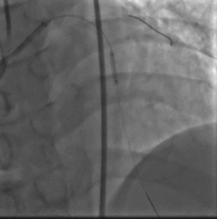

取0.014" Runthrough NS导丝通过病变送入高位钝缘支远端(图4),送入Atlantis SR血管内超声导管至左主干远段,未见明确前降支开口影像,0.014" Sion导丝未能通过前降支近段支架内闭塞病变处,换用0.014" ConquestPro导丝成功通过前降支近段支架内闭塞病变送至前降支中段(图5、6),换入0.014" Sion导丝至前降支远端,Sprinter Legend 2.5×15 mm球囊锚定导丝后,再以该球囊成功通过闭塞病变,反复以10~12 atm×5 s扩张(图7)。复查造影显示前降支恢复TIMI 3级血流,前降支近段处残余狭窄50%,中段局限性狭窄70%(图8)。Sprinter Legend 2.5×15 mm球囊以6 atm×8 s扩张前降支中段病变后,送入IVUS导管至前降支中段连续自动回撤示前降支中段心肌桥征象,近段弥漫性纤维斑块形成。植入Buma 3.5×25 mm雷帕霉素药物支架以10 atm×8 s扩张释放(图9),稍前送该支架球囊至两支架交界处以10 atm×8 s再次扩张塑形。行IVUS检查左主干内支架贴壁不良。取Quantum 4.5×12 mm高压球囊至左主干支架内以14~20 atm×8 s扩张塑形(图11),复查造影示支架扩张满意,残余狭窄<30%,血流TIMI 3级,回旋支血流未受影响(图12)。复查血管内超声示支架扩张满意,贴壁良好,支架两端无夹层征象。

图5、6